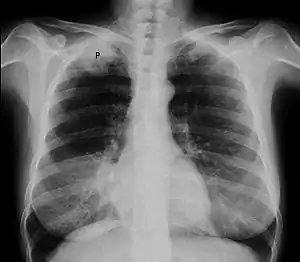

| Chest radiograph showing a Pancoast tumor (labeled as P, non-small cell lung carcinoma, right lung), from a 47-year-old female smoker. | |